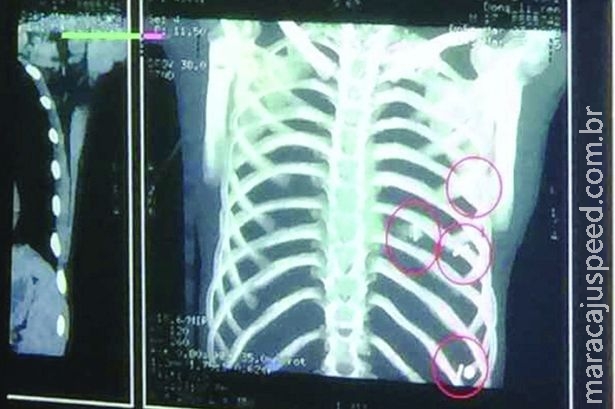

Médicos encontraram quatro agulhas no peito de um adolescente saudável que agora luta para andar.

Dong Liren, de 17 anos, da China, foi submetido a uma cirurgia de emergência depois que os médicos encontram quatro agulhas dentro de seu coração.

Duas das agulhas possuíam 5 centímetros e perfuraram em 4 centímetros seu coração.

Outras duas agulhas permanecem no corpo de Liren, mas os cirurgiões não foram capazes de removê-los no mesmo ato cirúrgico. Elas estão mais abaixo em sua caixa torácica.